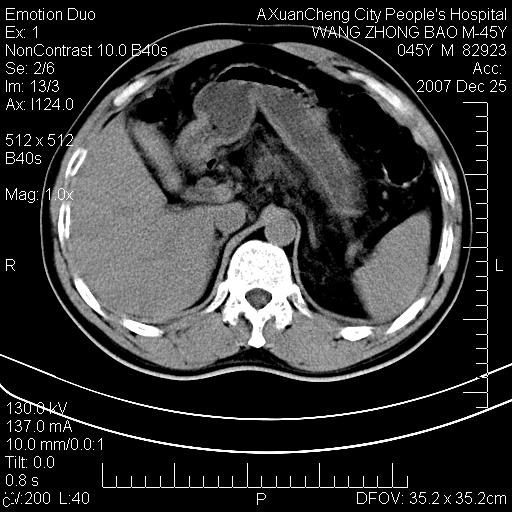

以下是引用卜一在2007-12-25 14:07:00的发言:[br]胰头钩部略增大,与十二指肠壶腹部关系密切,其内明显见软组织密度肿块,明显强化,但肠壁较光滑 柔软。考虑:炎性增生!建议消炎后复查!待除外壶腹部腺癌!

以下是引用zjzjr在2007-12-25 13:35:00的发言:[br]考虑正常的十二指肠乳头部,建议胃镜检查.

以下是引用qiuleiyu在2007-12-25 18:14:00的发言:[br]胰腺增大,周边渗出改变,肾前筋膜明显增厚,示少量积液.胆囊壁毛糙,周边少许渗出,胆总管壁厚,异常强化,然扩张不明显.结合病程急短;考虑;胆管炎,胆囊炎,胆源性胰腺炎可能大,请结合实验室检查及随访.

以下是引用lisihao在2007-12-25 14:23:00的发言:[br]急性水肿型胰腺炎[br]依据:1、胰腺弥漫性肿大,边缘稍毛糙;[br] 2、双侧肾周筋膜增厚,尤以左侧为甚(重要征象)[br] 3、双侧后胸膜增厚(刺激性炎症);[br] 4、结合病史,查血尿淀粉酶应该可以确诊。